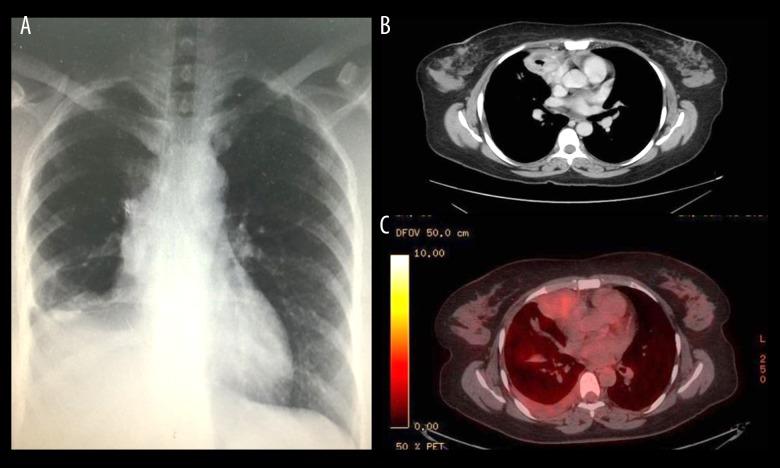

BACKGROUND Leiomyomas are benign neoplasms of the smooth muscle. When found in the pulmonary system, a rare occurrence, leiomyomas can result in hypertrophic osteoarthropathy, or significant clubbing, associated with proliferation of long bone periosteum. Bronchopulmonary fistulas, or communications between the bronchial tree and pleural space, are an uncommon postoperative complication of pneumonectomies. Even more infrequent is the presence of a bronchopulmonary fistula that is determined to be sterile. CASE REPORT The patient presented in the current case report is a 40-year-old previously healthy woman who presented with a 5-year history of chronic cough, right-sided chest discomfort, and dyspnea associated with back pain, and lower leg pain. The CT scan performed on the patient revealed a mass originating from the right lower lobe. Activity at the site of the lesion, in the long bones of the upper and lower limbs, rib cage, and vertebral bones was demonstrated by a bone scan. A CT-guided biopsy was performed, and the pathology report confirmed the presence of a leiomyoma. Following a right-sided lobectomy, the resected tumor was sent for histopathology, with the results confirming the biopsy. The patient subsequently presented with a history of persistent cough associated with increased watery secretions. The CT scan revealed the presence of a bronchopleural fistula, after which the patient underwent surgical correction. All symptoms resolved, and the patient was discharged in stable condition. CONCLUSIONS Here, we report on a patient who presented with 3 rare clinical findings: pulmonary leiomyoma, hypertrophic osteoarthropathy, and sterile bronchopulmonary fistula.

背景 平滑肌瘤是平滑肌的良性肿瘤。当在肺部系统发现时(这种情况很少见),平滑肌瘤可导致肥大性骨关节病或明显的杵状指,伴有长骨骨膜增生。支气管肺瘘,即支气管树与胸膜腔之间的连通,是肺切除术后一种不常见的并发症。更罕见的是发现无菌性支气管肺瘘。病例报告 本病例报告中的患者是一名40岁的既往健康女性,有5年慢性咳嗽、右侧胸部不适、伴有背痛和小腿疼痛的呼吸困难病史。对该患者进行的CT扫描显示右肺下叶有一个肿块。骨扫描显示病变部位、上肢和下肢长骨、肋骨和椎骨有活动。进行了CT引导下活检,病理报告证实存在平滑肌瘤。右侧肺叶切除术后,将切除的肿瘤送去做组织病理学检查,结果证实了活检结果。该患者随后出现持续咳嗽并伴有水样分泌物增多的病史。CT扫描显示存在支气管胸膜瘘,之后患者接受了手术矫正。所有症状均缓解,患者出院时病情稳定。结论 在此,我们报告了一名出现3种罕见临床发现的患者:肺平滑肌瘤、肥大性骨关节病和无菌性支气管肺瘘。